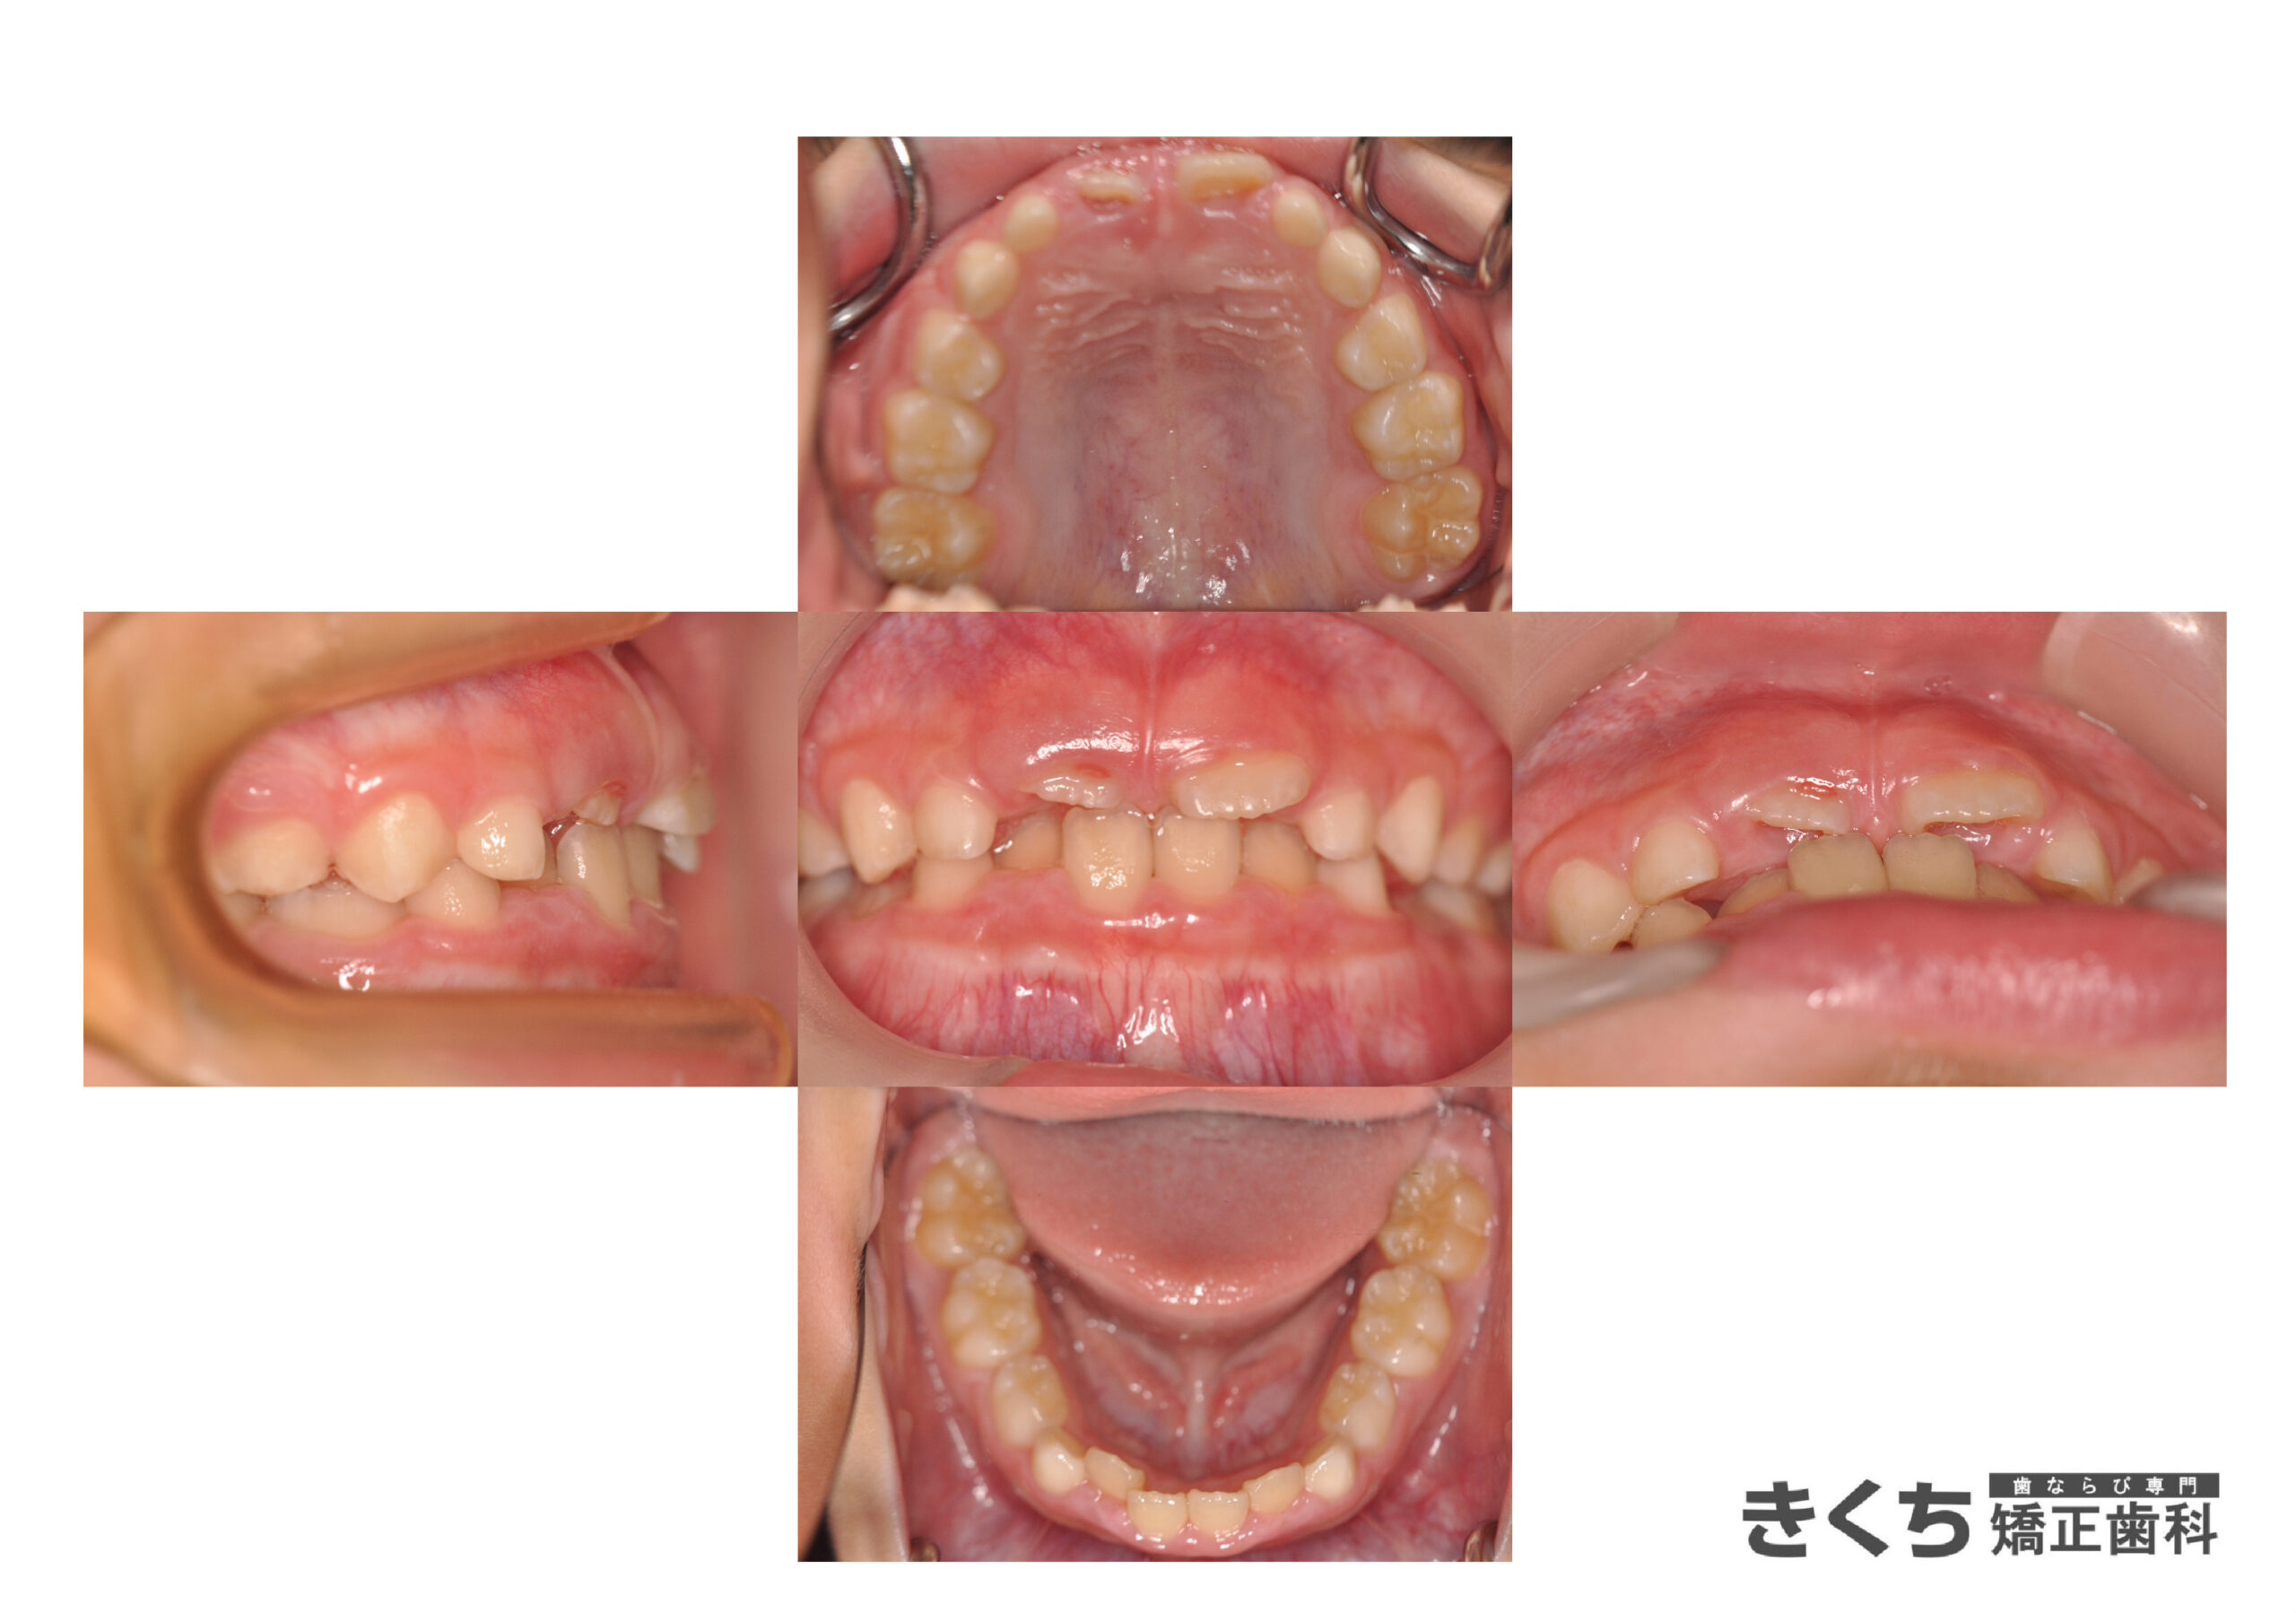

初診時7歳、かみ合わせを気にして来院

今すぐ矯正治療を始めたほうがいいと指摘を受けた

→6ヶ月ごとのペースで経過観察

口腔筋機能を改善するために指導を行いました。

↓↓↓↓↓↓↓ 6ヶ月後